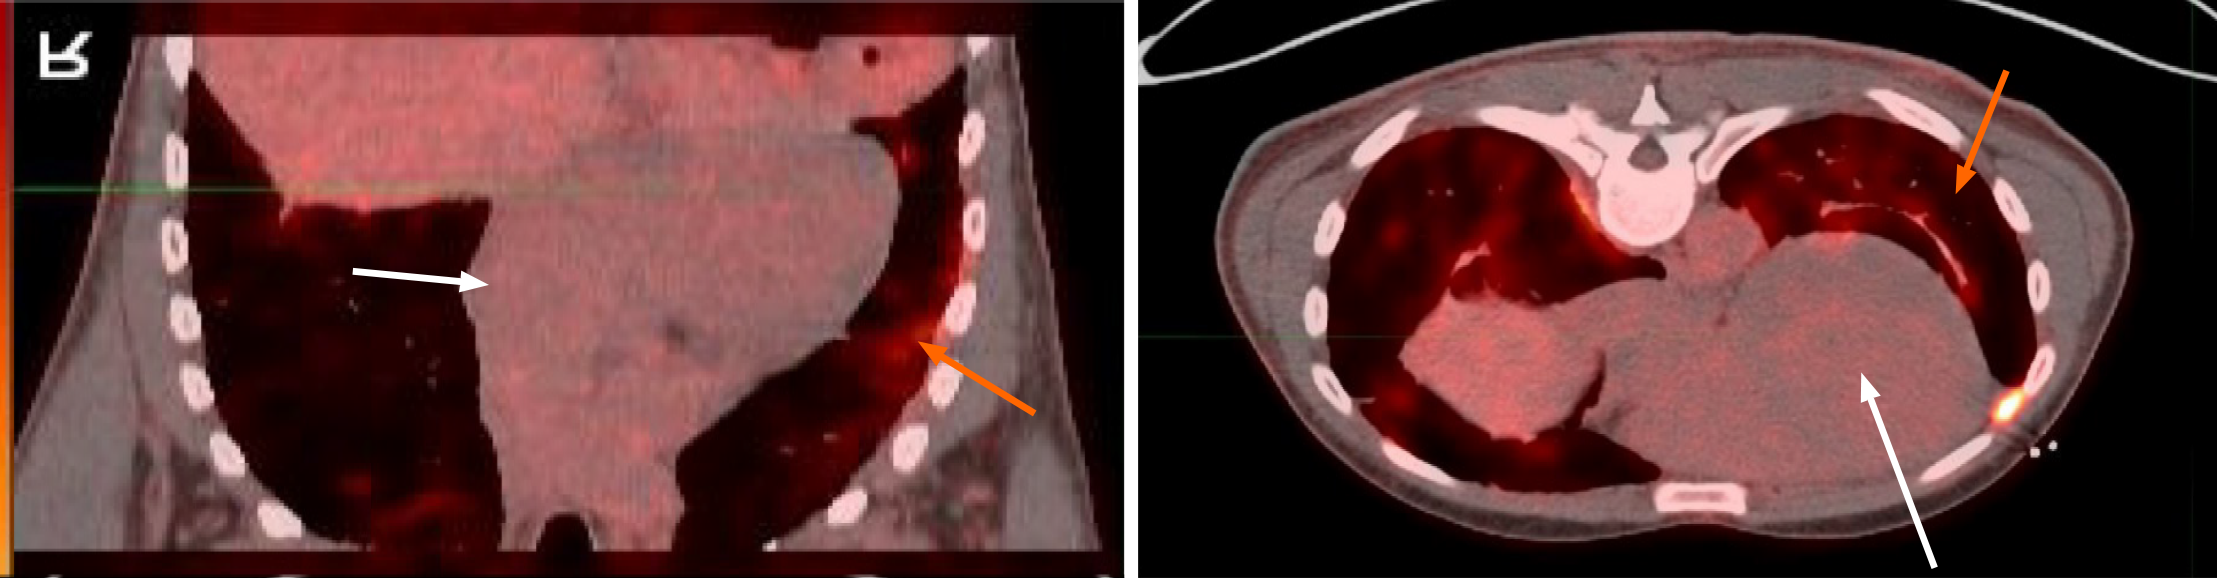

Endoscopic bronchial ultrasound with bronchoalveolar lavage showed increased CD4: CD8 ratio without malignant cells. cMRI was performed and showed LV dilation with severe systolic dysfunction, global hypokinesis, and LGE (Figure 4). Whole body PET revealed patchy perfusion abnormalities in the basal to mid inferior wall and mid septal segments (Figure 5). It also revealed FDG uptake in the lungs without FDG uptake in the heart. Left heart catheterization showed normal coronary arteries, right sided pressures, pulmonary vascular resistance index, pulmonary capillary wedge, left ventricular end diastolic pressure, cardiac output, and valvular function.

| Day 9 | Positron emission tomography has system FDG but no cardiac FDG, confirming active systemic sarcoidosis (SS) and burnt CS. ACL and B2M antibodies are positive, raising concern for APP and antiphospholipid syndrome. Medical and device therapy are begun for burnt CS and prednisone for SS |